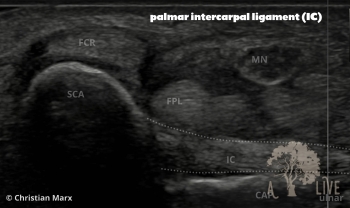

carpal ligaments